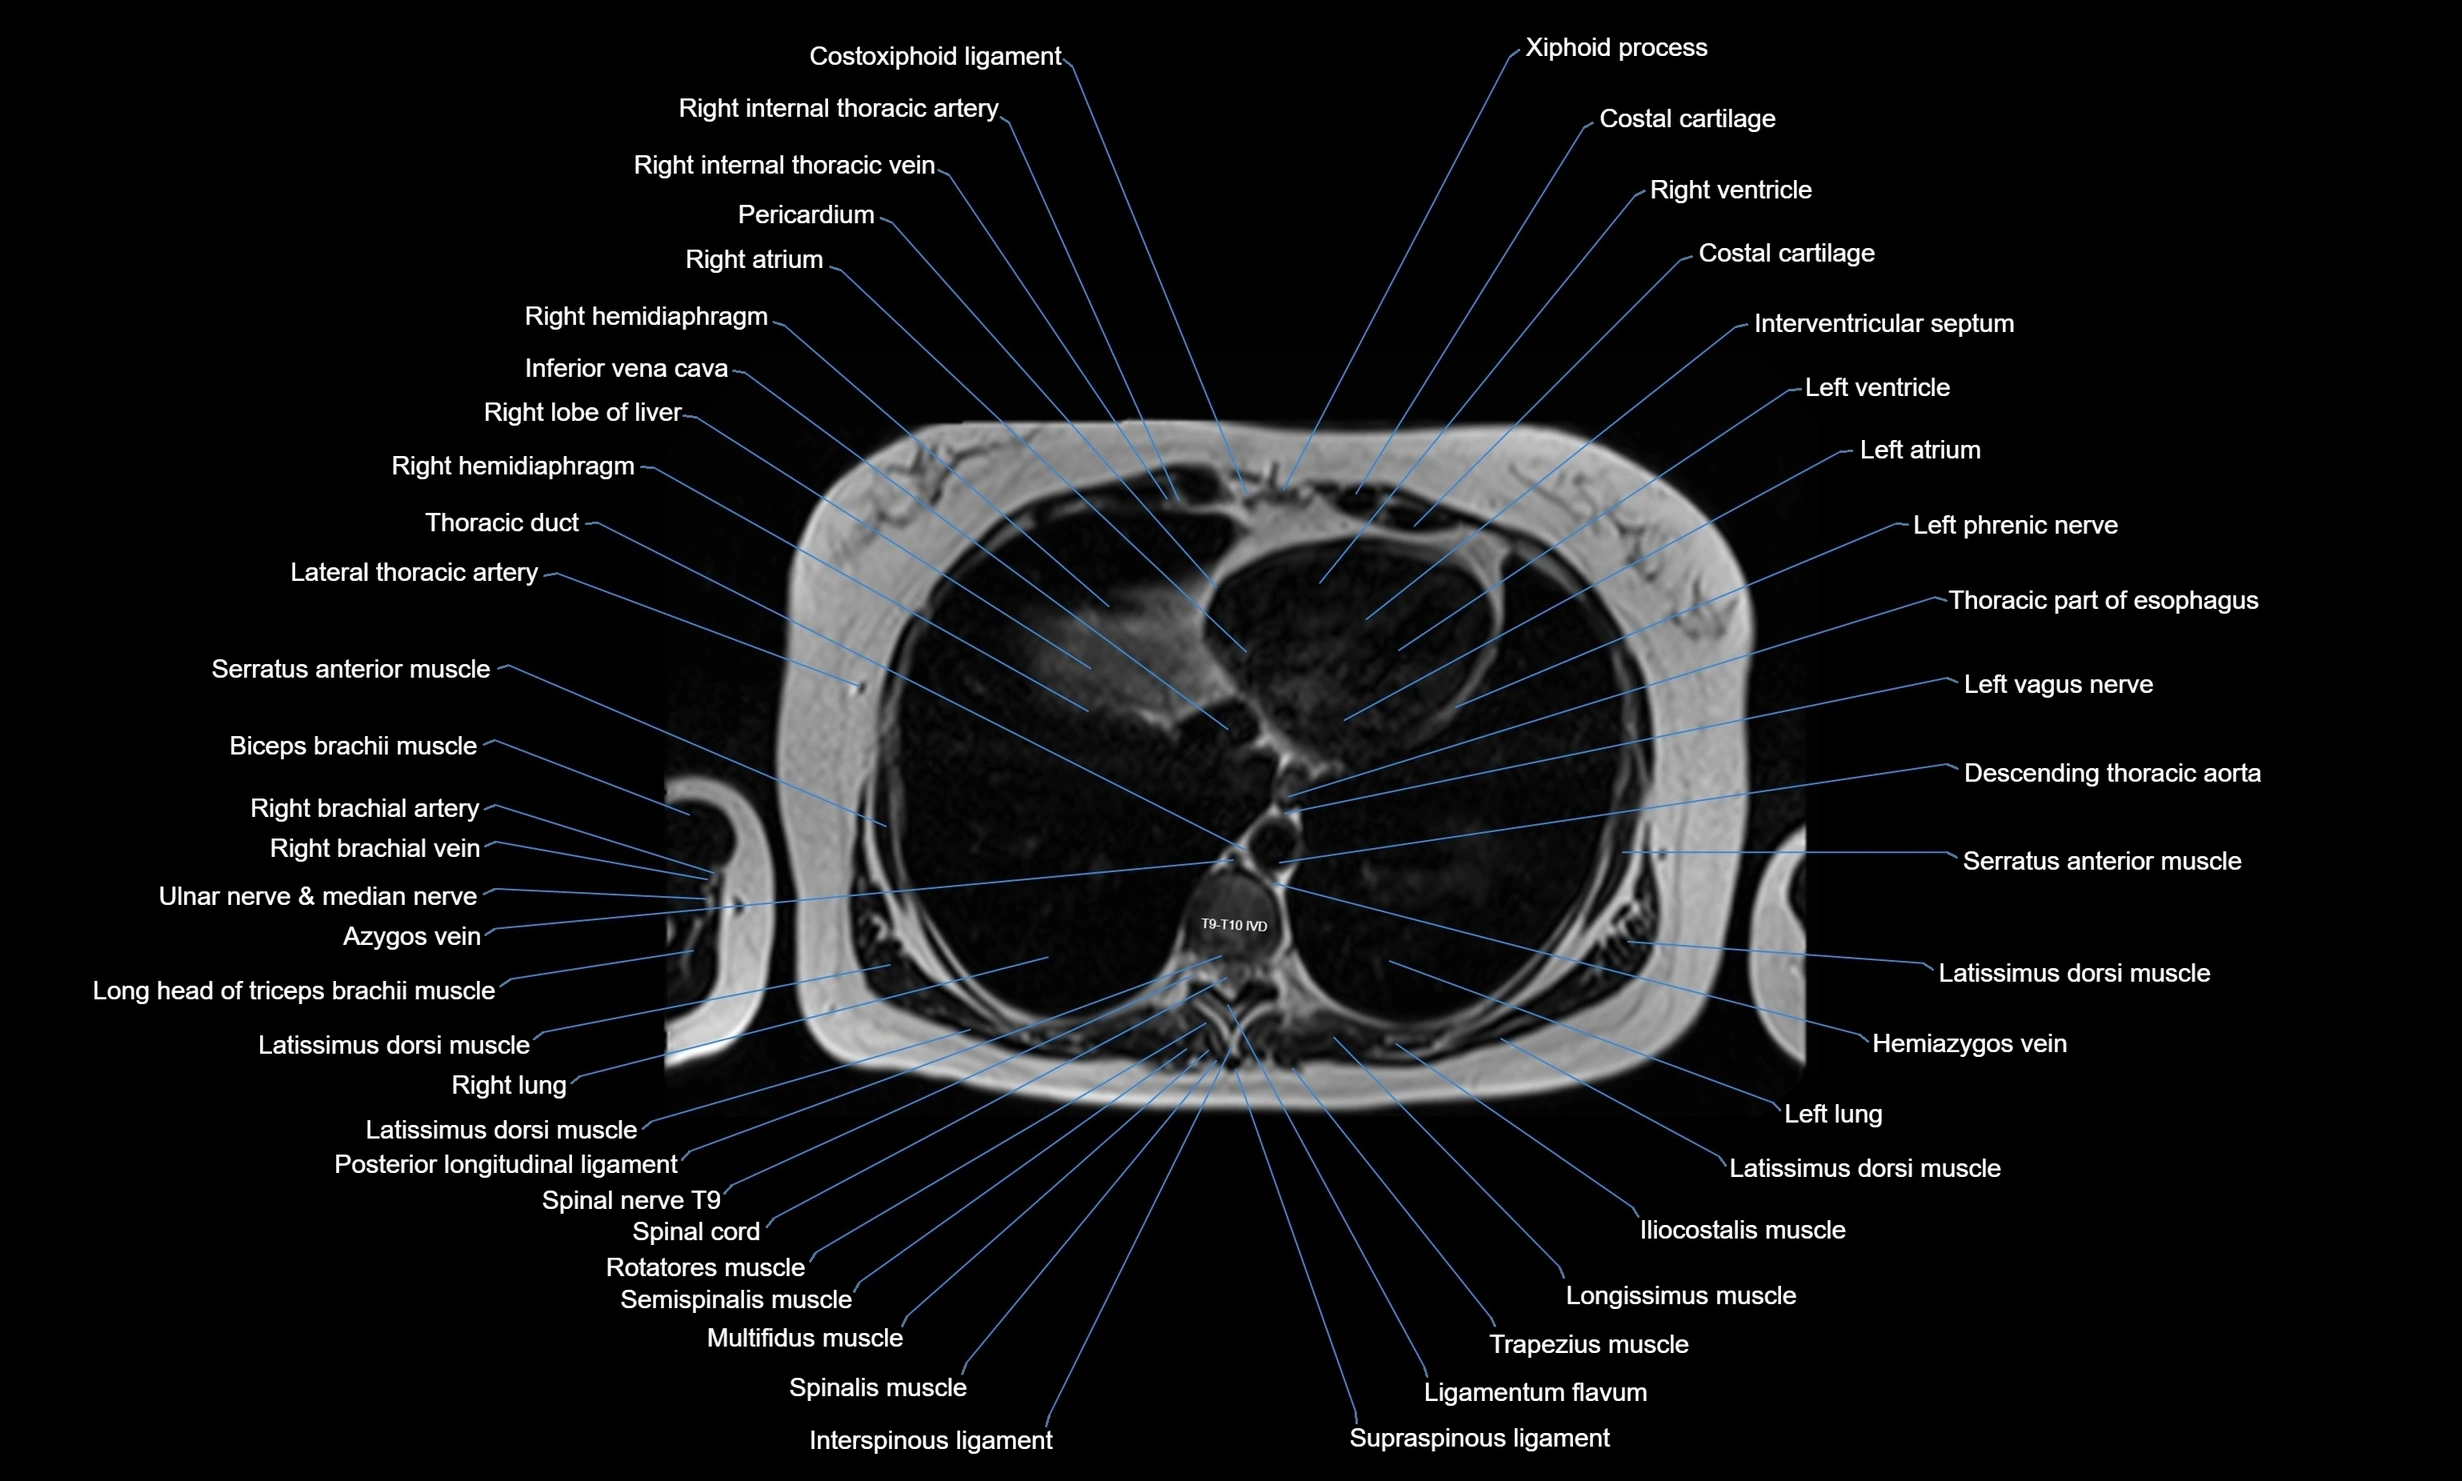

- T (Thoracic spine)